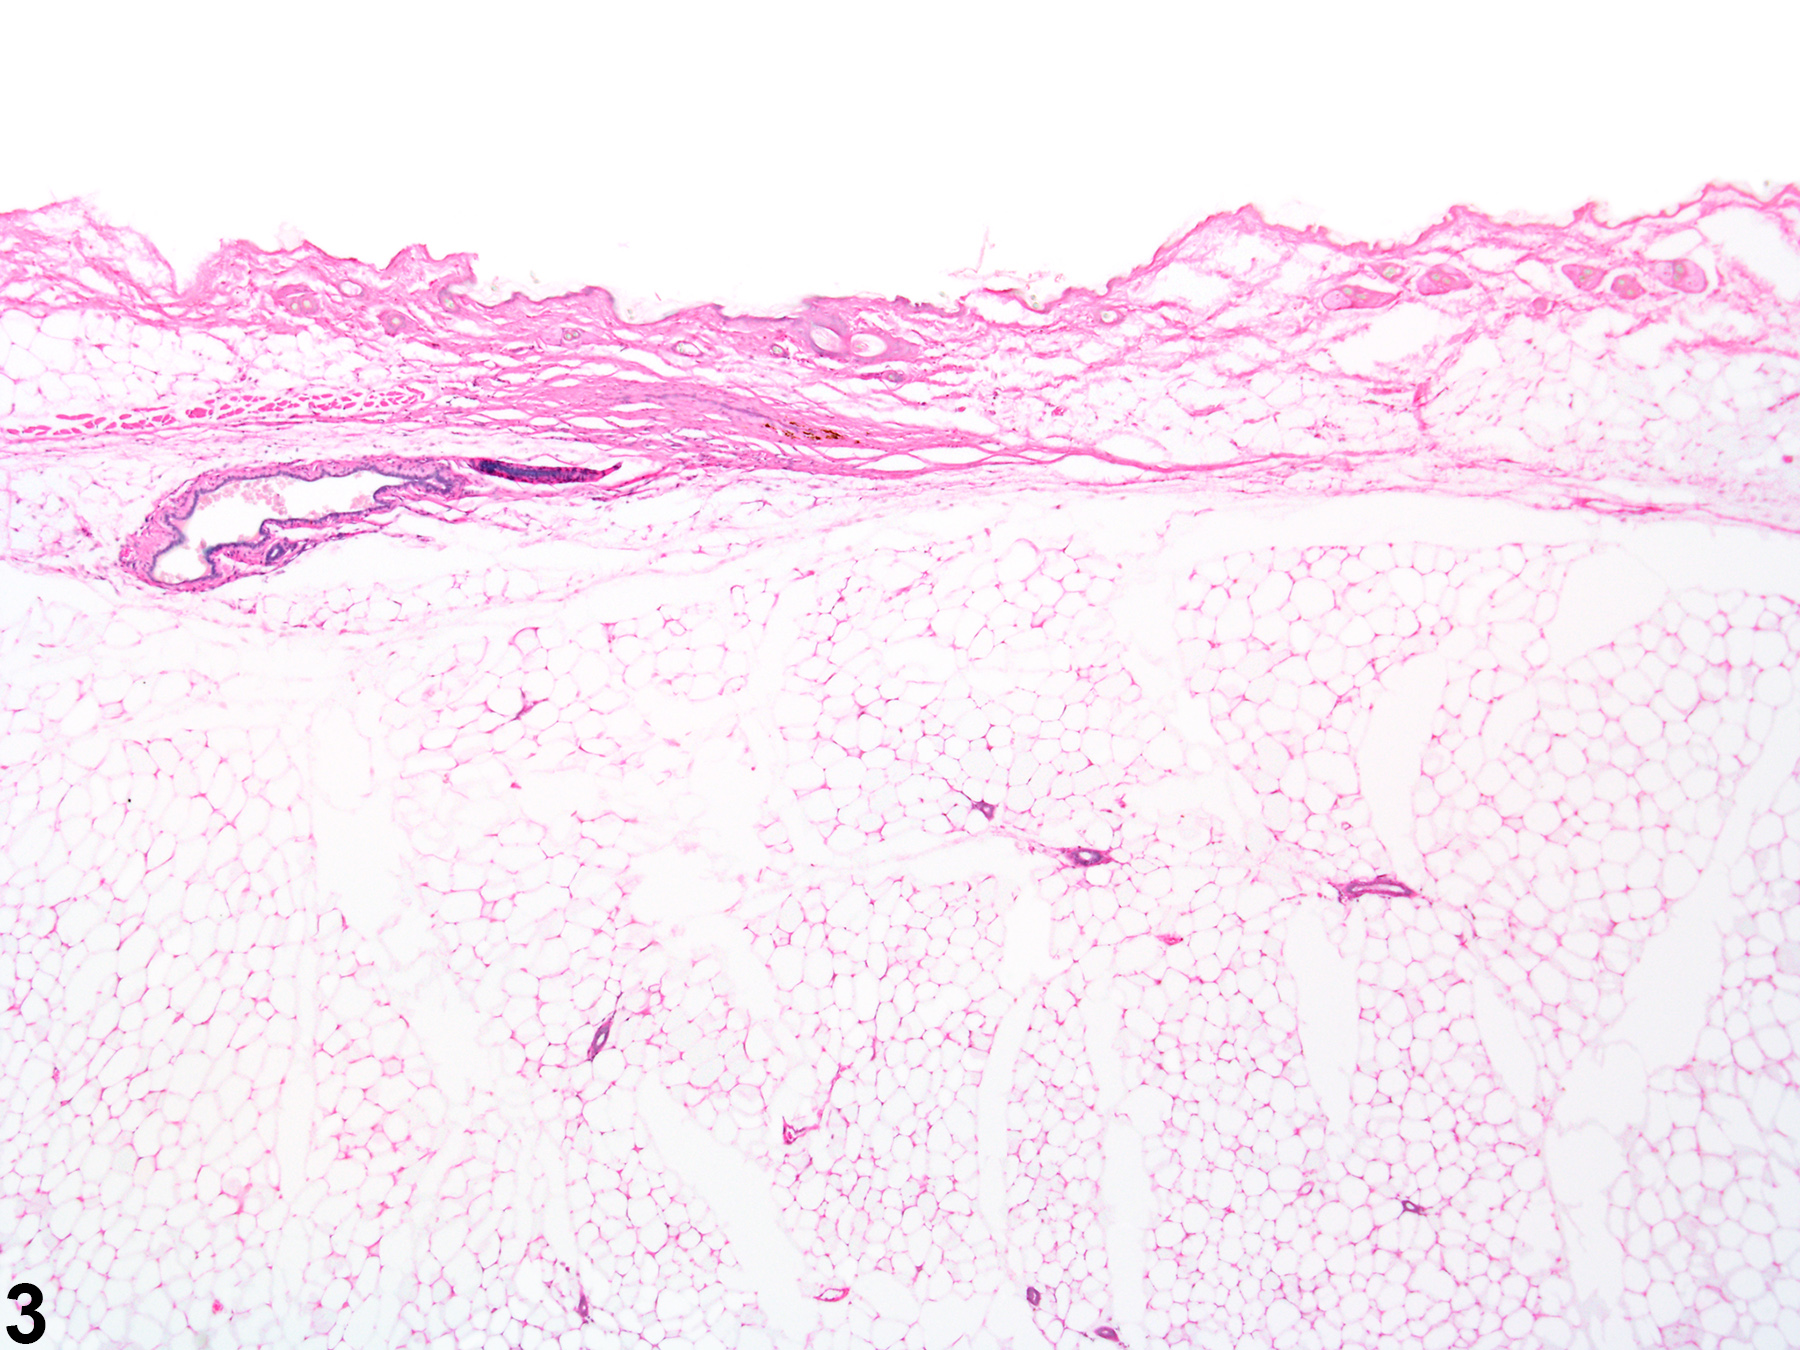

Diffuse atrophy of the normal alveolar (acinar) (Figure 1, Figure 2, Figure 3, and Figure 4) and ductular (Figure 3 and Figure 4) tissue of the mammary gland of rats and mice is an uncommon finding. It is most often associated with compound administration. Involution of the mammary gland begins in the second year of life in rats and mice and is characterized by loss of distal ducts in mice, and regression of terminal end buds and decrease in size of lobules in rats. This change, of course, would be present in both treated and control animals. Treatment with certain xenobiotics for long periods can induce hormonal perturbations, such as hypoestrogenism or estrogen receptor (ER) antagonism in rats that causes atrophy of the female mammary gland. With atrophy of the female mammary glands, the ductular and acinar components are both affected, resulting in a prominent appearance of the mammary gland fat pad. The epithelial cells lining the affected ducts and acini are low cuboidal and have a high nuclear cytoplasmic ratio. The term feminization refers to the conversion of the normally lobuloalveolar pattern of male rat mammary glands to the tubuloalveolar pattern seen in female rats and thus differs slightly from atrophy. Tamoxifen and toremifene are selective estrogen receptor modulators (SERM) and are examples of potent estrogen receptor antagonists in the rat mammary gland that cause ductal atrophy (and ectasia) in females and acinar atrophy in males. Care must be taken during tissue sectioning to prevent the erroneous appearance of atrophy during histopathologic evaluation.

Mammary gland - Normal in a female B6C3F1/N mouse from an acute study. Normal mammary gland with well-developed mammary fat (adipose) pad and age appropriate ductular and acinar tissue.